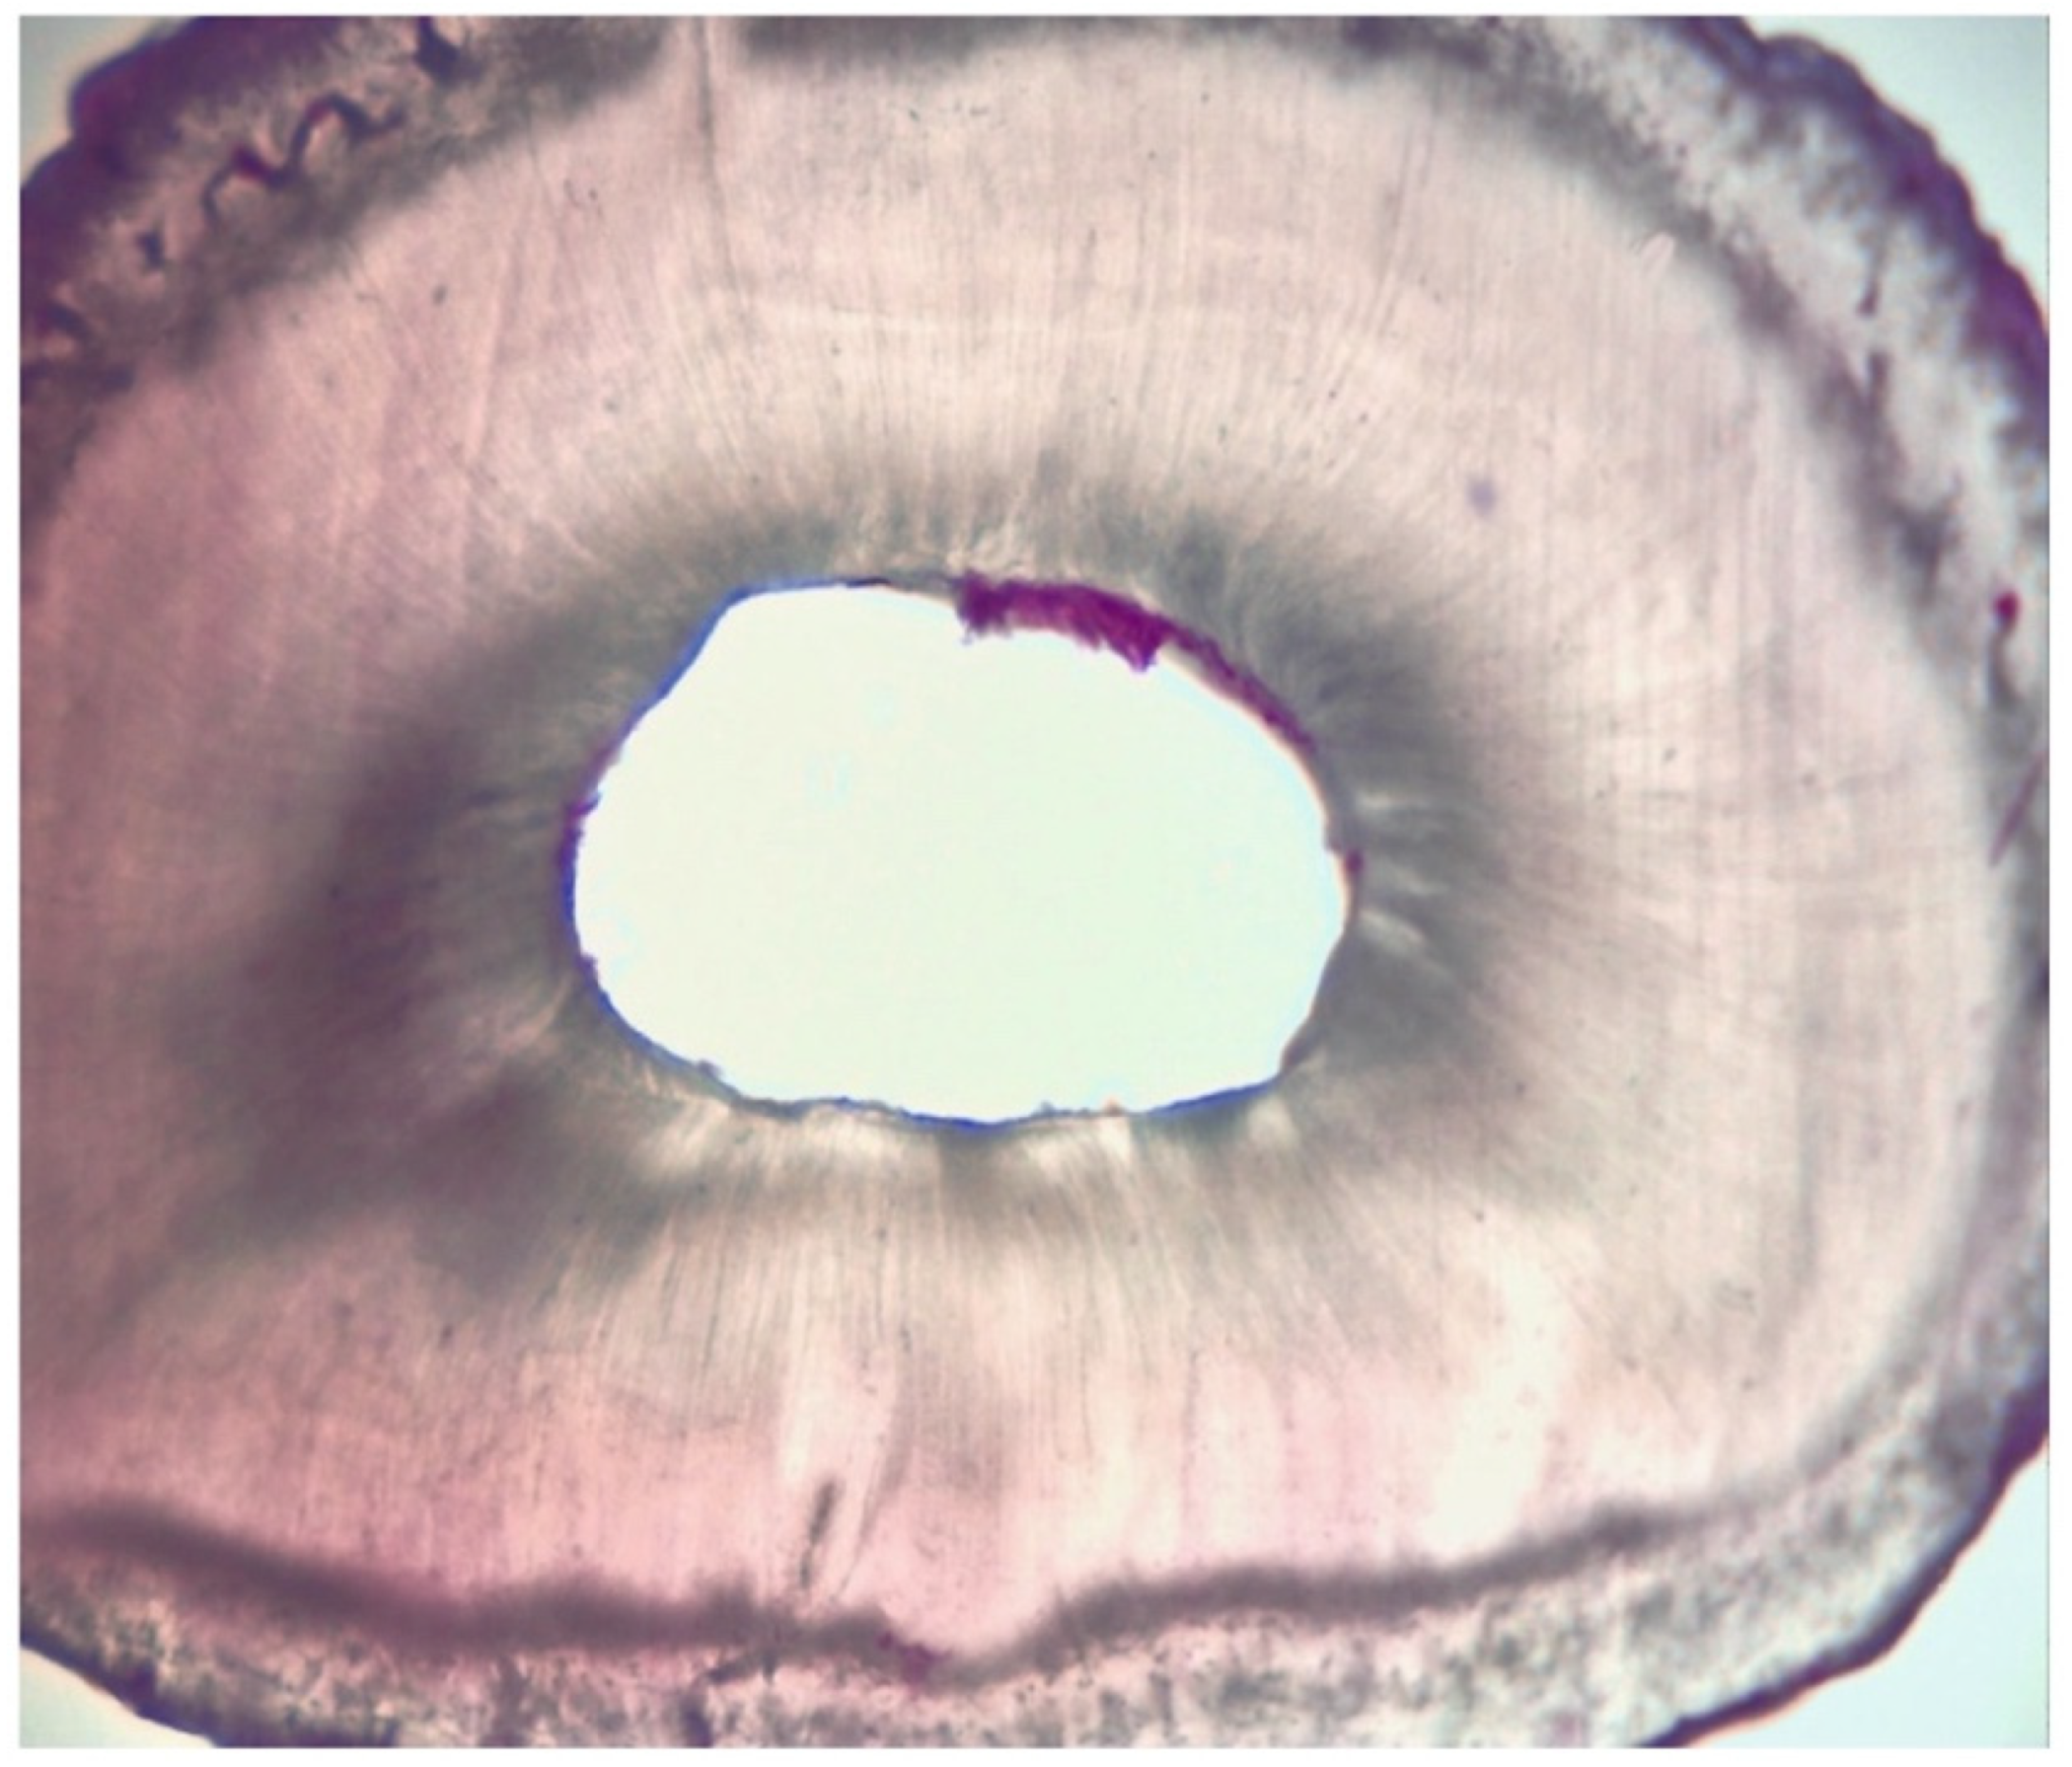

2.3. Assessment of Root Canal Cleanliness

| Grading | |

|---|---|

| I | presence of debris within the area |

| II | presence of debris in more than 50% of the entire area |

| III | presence of debris in more than 25% of the entire area |

| IV | absence of debris or presence of debris in less than 25% of the entire area |

| Group 1 | 2 [0.5] A |

| Group 2 | 4 [1] B |

| Score | I | II | II | I | II | III | II | II | II | I | II | I | II | III | II | II | III | II | I | II |

| Score | III | IV | IV | III | IV | III | III | IV | III | IV | IV | III | IV | IV | III | III | IV | IV | IV | IV |